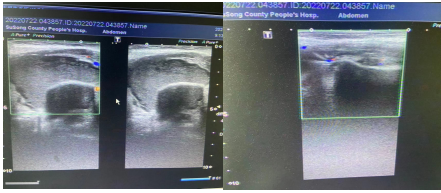

典型病例1 腮腺脓肿穿刺抽脓+灌洗注药治疗

治疗前 治疗后

术后针眼大小伤口